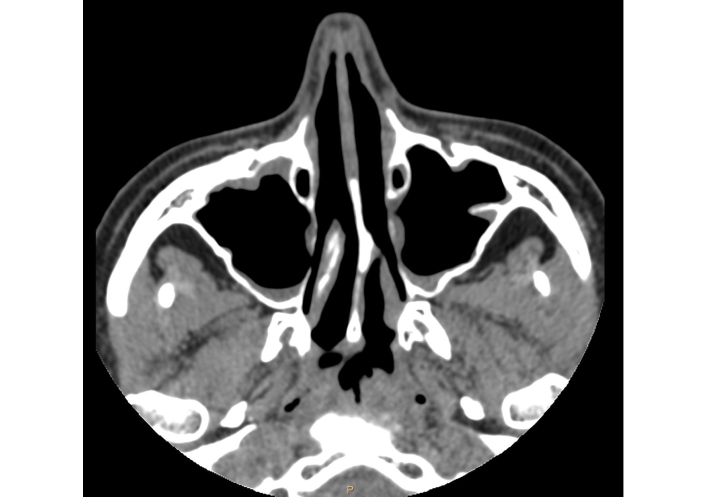

The return of her sense of smell and a significant improvement in the severity of nasal symptoms (TNSS, 6 points; SNOT-22, 23 points), quality of life (AQLQ, 6.9 points) and asthma control (ACQ, 2.3 points) were observed. The endoscopic examination did not reveal any nasal polyps (NPS, 0 point). The total IgE level was 590 UI/mL. In accordance with the National Health Fund requirements, after two years of biological treatment, we were obliged to withdraw biological treatment. The patient’s clinical condition critically worsened two months after withdrawal of the last dose of omalizumab. The patient reported loss of smell and significant nasal obstruction. There was also an exacerbation of asthma requiring intake of systemic steroids. A decision was made to restart treatment with omalizumab, followed by a rapid general clinical improvement. In the 5th year of therapy, a CT scan performed by a neurologist due to headaches showed complete remission of inflammatory changes in the paranasal sinuses (Figure 3).

Computed tomography scan of the patient’s paranasal sinuses after 5 years of biological treatment.